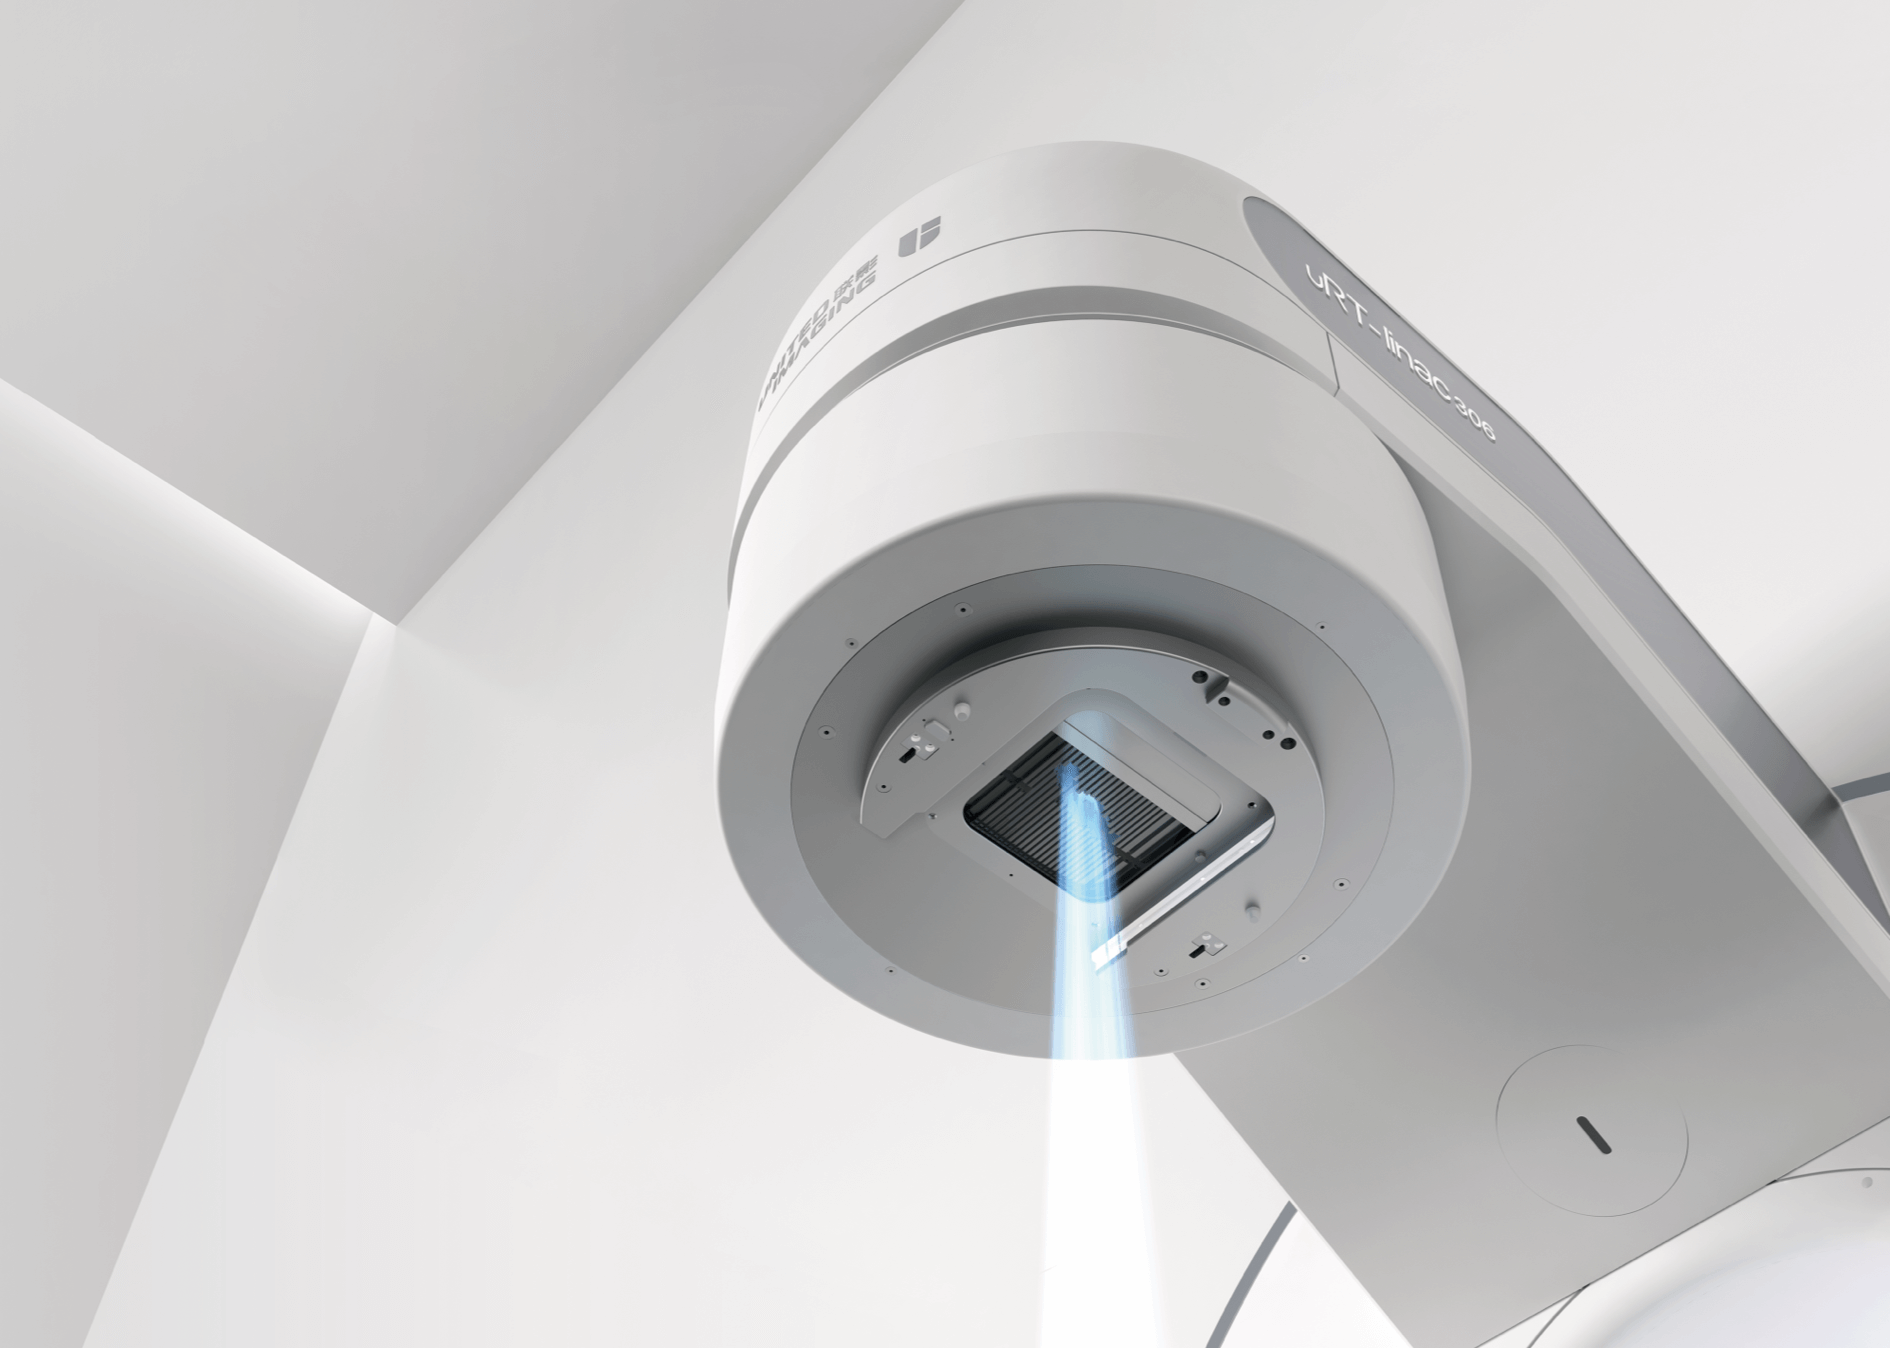

先进精准放疗系统

精准放疗触手可及

uRT-linac 306以同源双束的高清图像引导、全智能的放疗技术平台,覆盖智能勾画、计划、治疗与质控等全闭环流程,提升放疗同质化水平,让高端医疗惠及更多生命。